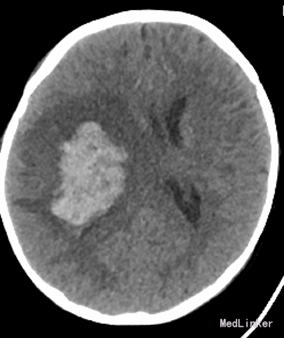

查体:T:36.8℃,P:173次/分,R:30次/分。神志清楚,舌下见约3*2cm水泡,左侧肢体肌力3级,右侧肢体肌力5级。辅助检查:院外CT:右侧基底节区出血。右侧基底节-顶叶区脑出血,大小约5.2cm×3.3cm,周围见大片状水肿带,右侧脑室受压变窄,中线结构左侧移位,环池不对称。CTA示:未见确切异常。全脑血管造影提示:颅内血管未见异常。寄生虫检查示:“猪囊尾蚴IgG阳性,血常规提示缺铁性贫血。

诊断:右侧基底节区顶叶出血,猪囊尾蚴病,缺铁性贫血。给予神经节苷脂钠,甘露醇注射液治疗。